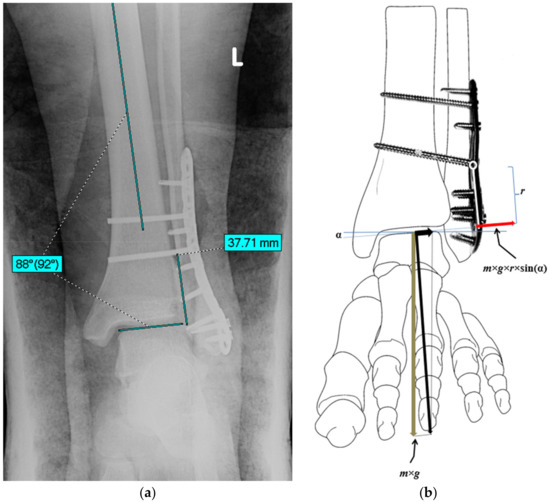

2.2. An Estimation of the Bending Moment Acting on the Plate